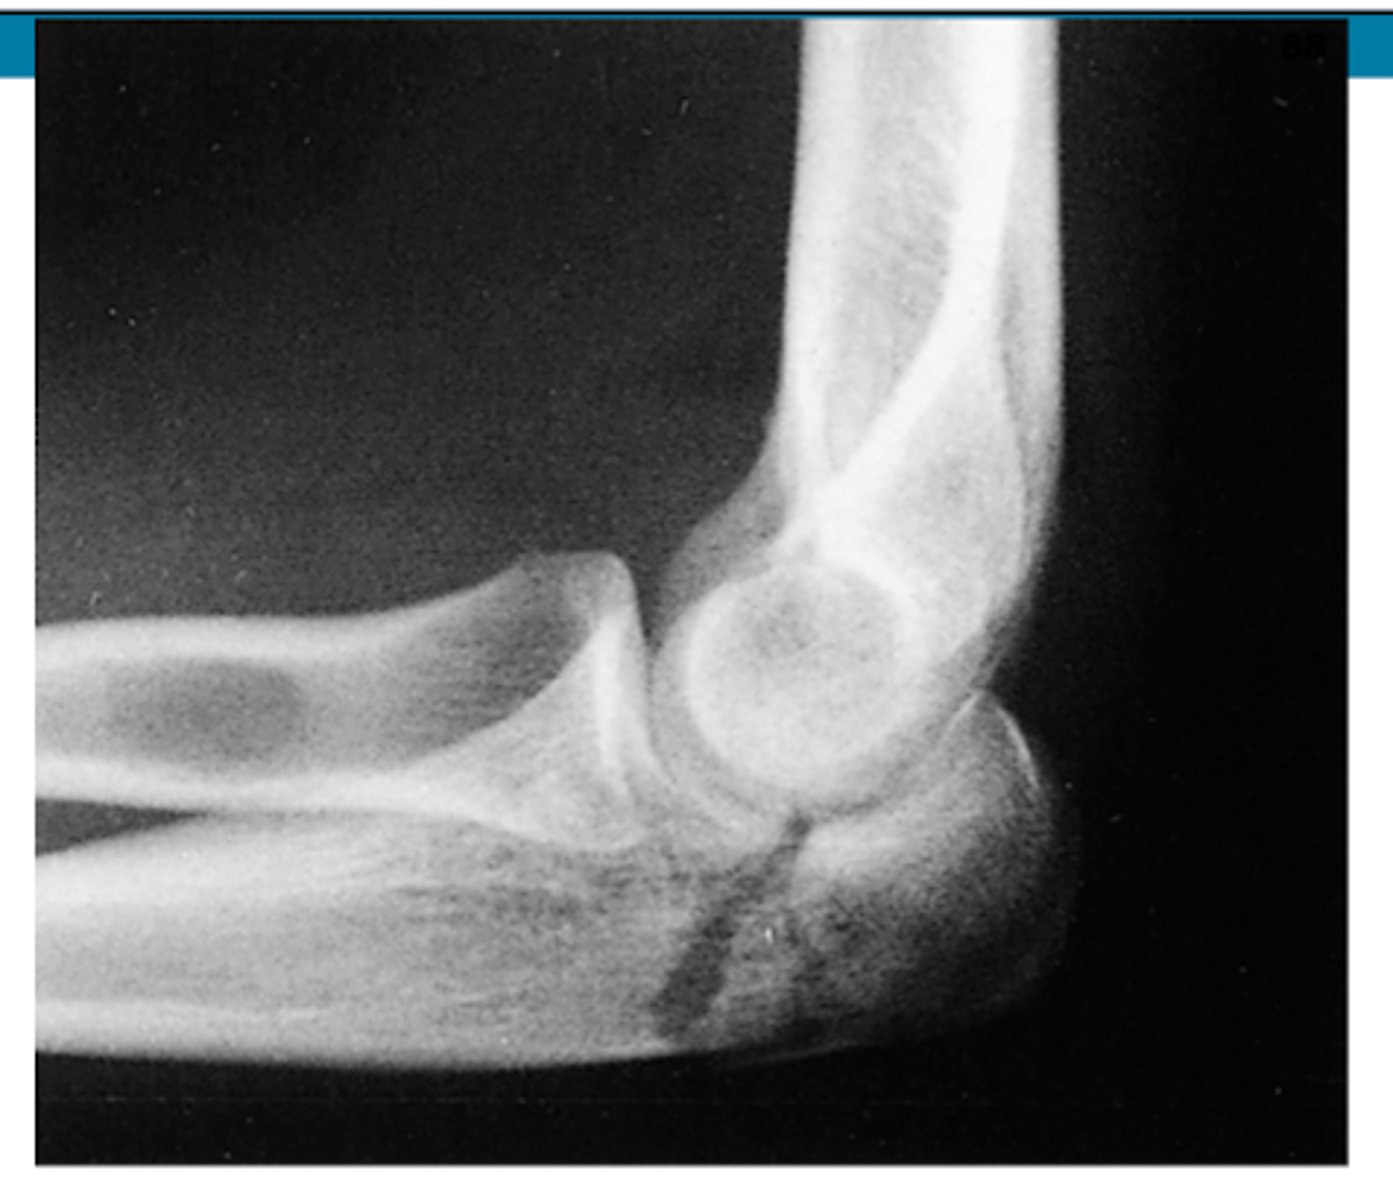

REVIEW: XR of elbow (lateral view)

REVIEW: XR of elbow #2 (lateral view)